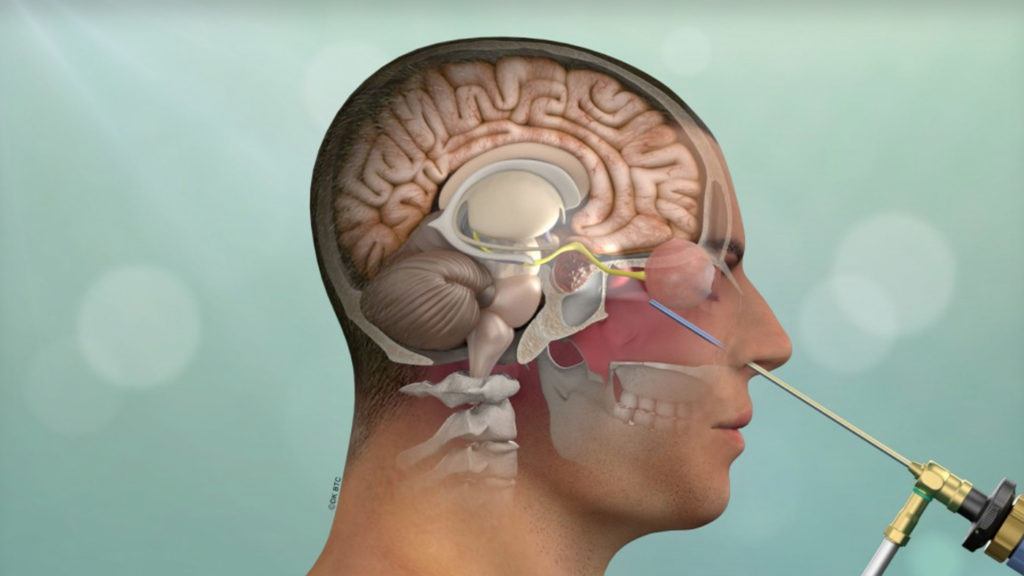

Brain Tumour Surgery

We offer advanced surgical treatment for both benign and malignant brain tumours, with an emphasis on maximal tumour removal while preserving neurological function. Conditions treated include gliomas, meningiomas, cerebellopontine (CP) angle tumours, pituitary adenomas, and intraventricular tumours.

Surgeries are carefully planned using modern imaging and microsurgical techniques to achieve optimal outcomes and ensure safe, effective tumour management for all types of brain tumours.